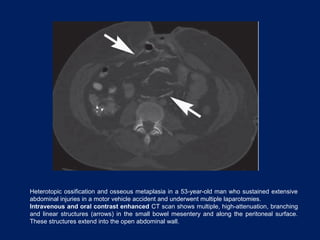

3- Osseous Metaplasia

•Osseous metaplasia of the mesentery and peritoneum.

•An unusual lesion that can develop after trauma or repeated

intraabdominal operative procedures.

•More frequently in men.

•It may represent metaplasia of the submesothelial mesenchyme or

implantation of osteoblasts or periosteum during trauma or procedures.

CT:

•Multiple high-attenuation, linear-branching structures within the

mesentery that extend to the peritoneal surfaces.

Heterotopic ossification and osseous metaplasia in a 53-year-old man who sustained extensive

abdominal injuries in a motor vehicle accident and underwent multiple laparotomies.

Intravenous and oral contrast enhanced CT scan shows multiple, high-attenuation, branching

and linear structures (arrows) in the small bowel mesentery and along the peritoneal surface.

These structures extend into the open abdominal wall.